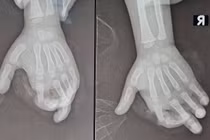

BS. Nguyễn Quang Vịnh, Khoa Phẫu thuật Chi trên và Vi phẫu thuật, Bệnh viện Trung ương Quân đội 108, ngày 1/7 cho biết, bệnh viện vừa cấp cứu bé gái 4 tuổi bị máy xay sinh tố nghiền vào bàn tay phải, gần đứt rời ngón thứ hai tay phải, chỉ còn dính lại gân gấp, trắng bệch do không được cấp máu.